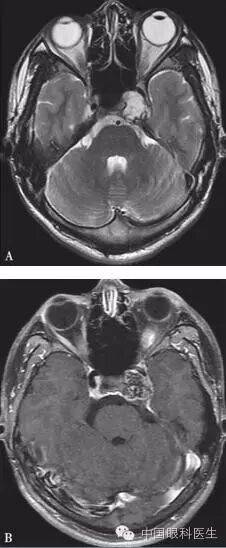

体格检查:双眼矫正视力0.8。右眼眼睑位置及眼球运动均正常,左眼上睑下垂,遮盖瞳孔上半部分,提上睑肌肌力4mm,左眼不能外展,上转、下转、内收运动均部分受限。患者右眼瞳孔直径3mm,左眼4mm;右眼对光反射灵敏,左眼迟钝,RAPD(-)。双眼眼底、眼压均正常。视觉诱发电位(visual evoked potential,VEP)、视野检查均未见明显异常。头颅MRI平扫+增强结果显示,左侧鞍旁海绵窦内T1WI稍低信号、T2WI稍高信号影,大小为21mm×23mm×22mm,增强扫描病灶呈不均匀强化,内可见多发的未强化区,左侧颈动脉海绵窦段受压外移,但结构未见明显损害(图2-3-0-1)。头颅CT平扫显示左侧鞍旁密度减低影,CT值为21Hu,大小为2.3cm,边缘可见钙化影,双侧眶内和球后未见异常(图2-3-0-2)。患者转入神经外科并行经额颞颧弓硬膜外入路左侧海绵窦区占位性病变切除术。术中快速冰冻切片病理学检查示,切除的组织标本富含黏液,制片困难。术后病理报告:左侧海绵窦区软骨源性肿瘤。考虑软骨瘤可能性大,局部细胞生长活跃,细胞间质伴黏液变性,免疫组织化学染色显示,肿瘤细胞对S-100和CK均呈阴性反应(图2-3-0-3)。术后患者左眼视力下降,额部及颊部皮肤感觉迟钝。眼科检查:右眼检查同术前,左眼矫正视力0.5,角膜上皮粗糙,角膜荧光素染色弥漫性着色,RAPD(-)。检眼镜检查示视盘界清,色红,视网膜血管走行正常,黄斑区未见明显异常。VEP、视野检查均未见明显异常。给予玻璃酸钠滴眼液点左眼、重组牛碱性成纤维细胞生长因子软膏涂左眼结膜囊并给予营养神经、改善全身血液循环药物治疗1周后,检查示见角膜上皮透明,角膜荧光素染色不明显,矫正视力0.8,左眼提上睑肌肌力测试可上提10mm。术后1个月复诊见,上睑下垂治愈,眼球运动受限明显好转。

注:A.软组织窗;B.骨窗。左侧鞍旁可见密度减低影,CT值21Hu,大小约为2.3cm,边缘可见钙化影,双侧眶内和球后未见异常